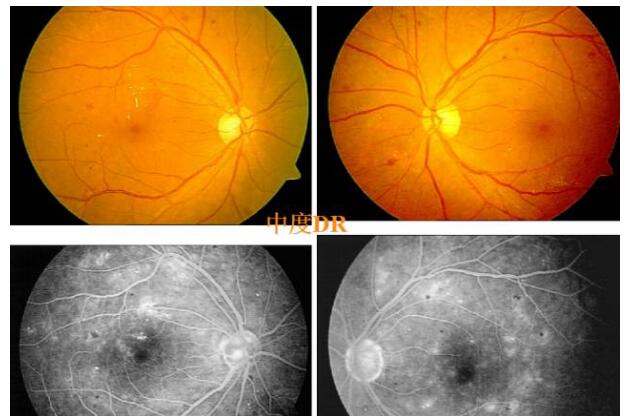

糖网病的眼底表现

微血管瘤

出血斑

渗出

视网膜静脉扩张、动脉变细、小血管闭塞

糖网病的检查手段

眼底照相:客观记录

眼底荧光血管造影:更清楚、更敏锐

对糖尿病病程10年和伴有轻微非增殖期DR病的病人,应建议半年进行一*次眼底检查,如伴有中期的DR和或糖尿病超过10年的病人应每三个月检查一*次。